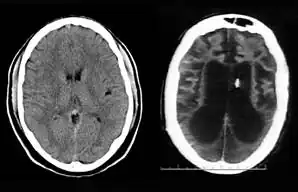

On August 10, 2001, on remand from the Florida Second District Court of Appeal, Judge Greer heard a motion from the Schindlers claiming that new medical treatment could restore sufficient cognitive ability such that Terri Schiavo herself would be able to decide to continue life-prolonging measures. The court also heard motions from the Schindlers to remove the guardian (Michael Schiavo) and to require Judge Greer to recuse himself. Judge Greer denied the motions and the Schindlers appealed to the Second District Court of Appeals. On October 17, 2001, the Court of Appeal affirmed the denials of the motions to remove and recuse. The Court of Appeals acknowledged that their opinion misled the trial court, and they remanded the question of Terri Schiavo's wishes back to the trial court and required an evidentiary hearing to be held. The court specified that five board certified neurologists were to testify. The Schindlers were allowed to choose two doctors to present findings at an evidentiary hearing while Schiavo could introduce two rebuttal experts. Finally, the trial court itself would appoint a new independent physician to examine and evaluate Terri Schiavo's condition. These decisions, all published in a single order by the Florida Second District Court of Appeal,[37] came to be known by the court as Schiavo III in its later rulings. In October 2002, on remand by the Second District Court of Appeal, an evidentiary hearing was held in Judge Greer's court to determine whether new therapy treatments could help Terri Schiavo restore any cognitive function. In preparation for the trial, a new computed axial tomography scan (CAT scan) was performed, which showed severe cerebral atrophy. An EEG showed no measurable brain activity. The five physicians chosen were William Maxfield, a radiologist, and four neurologists: William Hammesfahr, Ronald Cranford, Melvin Greer and Peter Bambakidis.[38]

The five doctors examined Terri Schiavo's medical records, brain scans, the videos, and Terri herself. Cranford, Greer, and Bambakidis testified that Terri Schiavo was in a persistent vegetative state (PVS). Maxfield and Hammesfahr testified that she was in a minimally conscious state. As part of the court-ordered medical exam, six hours of video of Terri Schiavo were taped and filed at the Pinellas County courthouse. The tape included Terri Schiavo with her mother and neurologist William Hammesfahr. The entire tape was viewed by Judge Greer, who wrote, Terri "clearly does not consistently respond to her mother". From that six hours of video, the Schindlers and their supporters produced six video clips intended to support their case, totaling less than six minutes, and released those clips to public websites.[1] Judge Greer ruled that Terri Schiavo was in a PVS, and was beyond hope of significant improvement. The trial court order was particularly critical of Hammesfahr's testimony, which claimed positive results in similar cases by use of vasodilation therapy, the success of which is unsupported in the medical literature.[39] This ruling was later affirmed by Florida's Second District Court of Appeal, which stated that "this court has closely examined all of the evidence in the record", and "we have ... carefully observed the video tapes in their entirety." The court concluded that "if we were called upon to review the guardianship court's decision de novo, we would still affirm it." This decision by the Second District Court of Appeals[40] came to be known as Schiavo IV in later rulings.